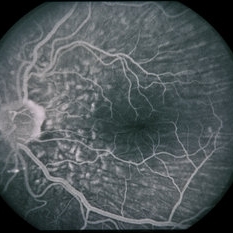

45-year-old Hispanic male with hypotony from over-filtration.